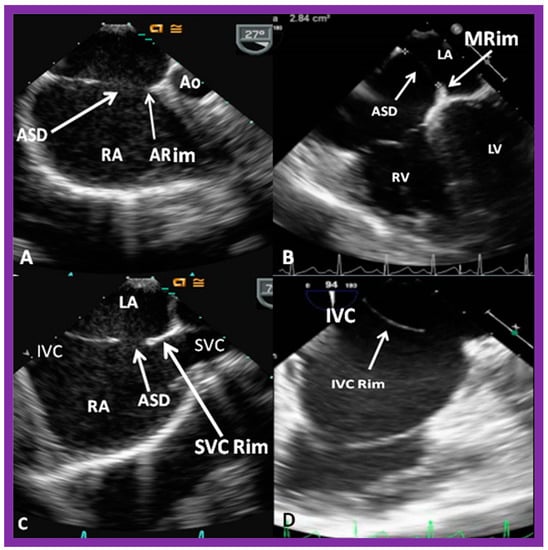

4. Patient Selection for Device Occlusion

8.5. Septal Rims